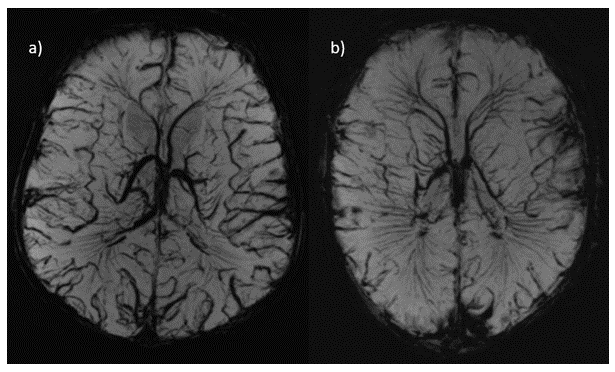

SVR of T2w images provided increased tissue contrast and SNR by combining multiple images into single 3D volumes while correcting for motion, as demonstrated in Figure4.

In our small cohort, we found that visualisation of anatomy was better appreciated at 7T on T2w imaging in comparison to 3T, notably in the hippocampus, cerebellum vermis, and cortical folding. This may be a direct result of increased SNR. SVR was found to be helpful in both ensuring full multi-planar visualisation and in removing artefacted slices. In general, the 7T SVR results provided more details than the corresponding 3T reconstructions.

Figure 4: SVR of the T2 images additionally provided correction for head motion during acquisition and further increases in tissue contrast and SNR. The top row shows the Native Data (axial slices) whereas the bottom shows the SVR isotropic volume.